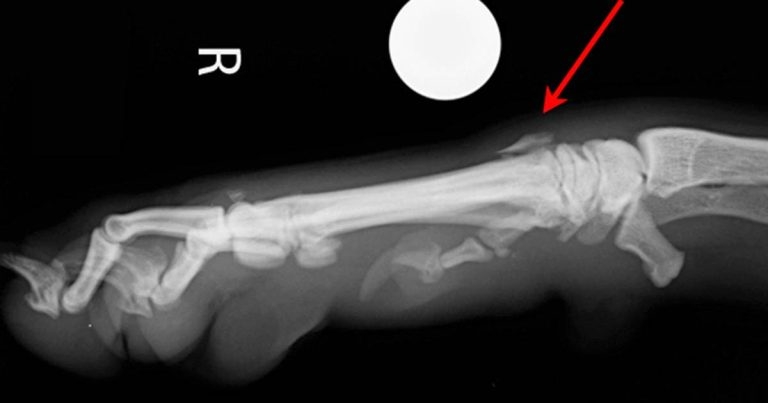

Figure 2. Mediolateral projection of the carpus showing metacarpal fracture (arrow).

On the mediolateral view (Figure 2), a fracture of the proximal aspect of either the third or fourth metacarpal can be appreciated, but it is difficult to localise this lesion accurately as the fragment cannot be visualised on the dorsopalmar projection.